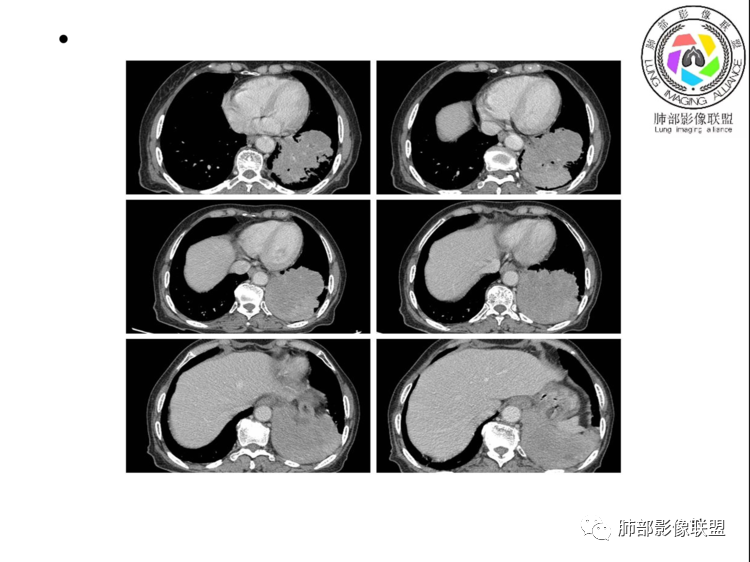

团片,内有支气管扩张,血管飘浮,不均匀强化,累膈肌似侵及脾脏,考虑恶性,淋巴瘤?肉瘤?

左肺下叶团块,边缘膨隆分叶,支气管部分阻塞、部分进入扩张,密度不均,延迟强化,血管走行正常,病灶与左侧膈肌分界不清。考虑恶性肿瘤:1淋巴瘤;2肉瘤样癌。

左肺下叶巨大实性肿块,支气管进入后阻塞,血管走行自然,增强中度均匀强化,无明显坏死。与膈肌分界不清,是否有侵犯导致腹痛症状?

老年女性,上腹部疼痛为主诉,CT所示左肺下叶肿块,左肺下叶支气管变窄,局部阻塞,病灶可见分叶,内见僵硬稍扩张的支气管,增强扫描病灶中度强化,内见血管造影征,首先考虑恶性病变,腺癌和淋巴瘤需要考虑,转移瘤待排除。

老年女性,以上腹痛就诊,左肺下叶团块影,边界清,可见分叶,延迟强化,内未见明显坏死,可见支气管充气扩张,血管走形自然,考虑淋巴瘤

老年女性,上腹痛就诊,CT可见左肺下叶巨大肿块,支气管进入后变窄堵塞,血管走行自然,内可见稍扩张支气管,增强均匀强化,与膈肌分界不清,考虑为恶性,淋巴瘤或腺癌可能

老年女性,左肺下叶软组织肿块,密度较均匀,边缘膨隆分叶,临近支气管截断,肿块内可见支气管穿行,与膈肌分界不清,增强后动脉期轻度均匀强化,静脉期呈渐进性强化,欠均匀,内血管走形如常,可见血管漂浮,整体感觉病灶偏软,考虑淋巴瘤可能大,鉴别腺癌。

患者老年女性,上腹部疼痛一周,无呼吸道症状,查体无阳性体征。血常规、尿常规、肝肾功能正常。肿瘤标志物CA125稍升高。胸部CT:左肺下叶肿块灶,边缘欠光滑,边界欠清楚,见分叶、血管集束征象,内见支气管扩张,增强中度强化,见血管漂浮征象。综合考虑恶性病变,淋巴瘤可能大,鉴别肺癌。

左下肺不规则巨大肿块,下叶支气管部分阻塞,部分扩张,与左侧膈肌分界不清,增强延迟强化,可见血管造影征,考虑恶性,淋巴瘤可能大,鉴别腺癌

老年女性,上腹部疼痛一周,肿标CA125升高。胸部CT:左肺下叶巨大肿块,分叶,密度不均,与左膈肌分界不清,内见枯枝征,部分支气管进入后截断,增强中度延迟强化,见血管漂浮征。胃壁不均匀增厚。考虑:恶性肿瘤病变伴阻塞性炎症,淋巴瘤?腺癌转移?鉴别TB、隔离等。